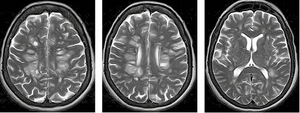

На рисунку 4 наведено МРТ-зображення головного мозку пацієнта з гострим геморагічним лейкоенцефалітом (хворобою Херста) у режимі Т2*/T2 GRE, де візуалізуються двобічні гіперінтенсивні вогнища, два з яких містять геморагічний компонент, та в режимі Т2. А на рисунку 5 — МРТ-зображення головного мозку пацієнта з ГРЕМ у режимі Т2 — продемонстровано важливу ознаку ГРЕМ (на відміну від РС): відносну інтактність мозолистого тіла, стовбура мозку, середніх мозочкових ніжок та мозочка, які в разі РС, як правило, уражаються першочергово. Вказана ознака не завжди є показовою, але має високу інформативність для диференційної діагностики.

/images/nn257-1622023r4_.jpg)

/images/nn257-1622023r5_.jpg)